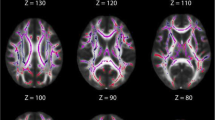

Lesion overlay maps of participant in the other pTBIs group (n = 169) grouped by lesion location. Numbers on the top of the brain slices indicate the z coordinates (MNI) of each axial slice. The color indicates the number of veterans in the group with damage to a given voxel. Images are in radiological space (i.e. right is left). For interpretation of the references to color in this figure legend, the reader is referred to the web version of this article.